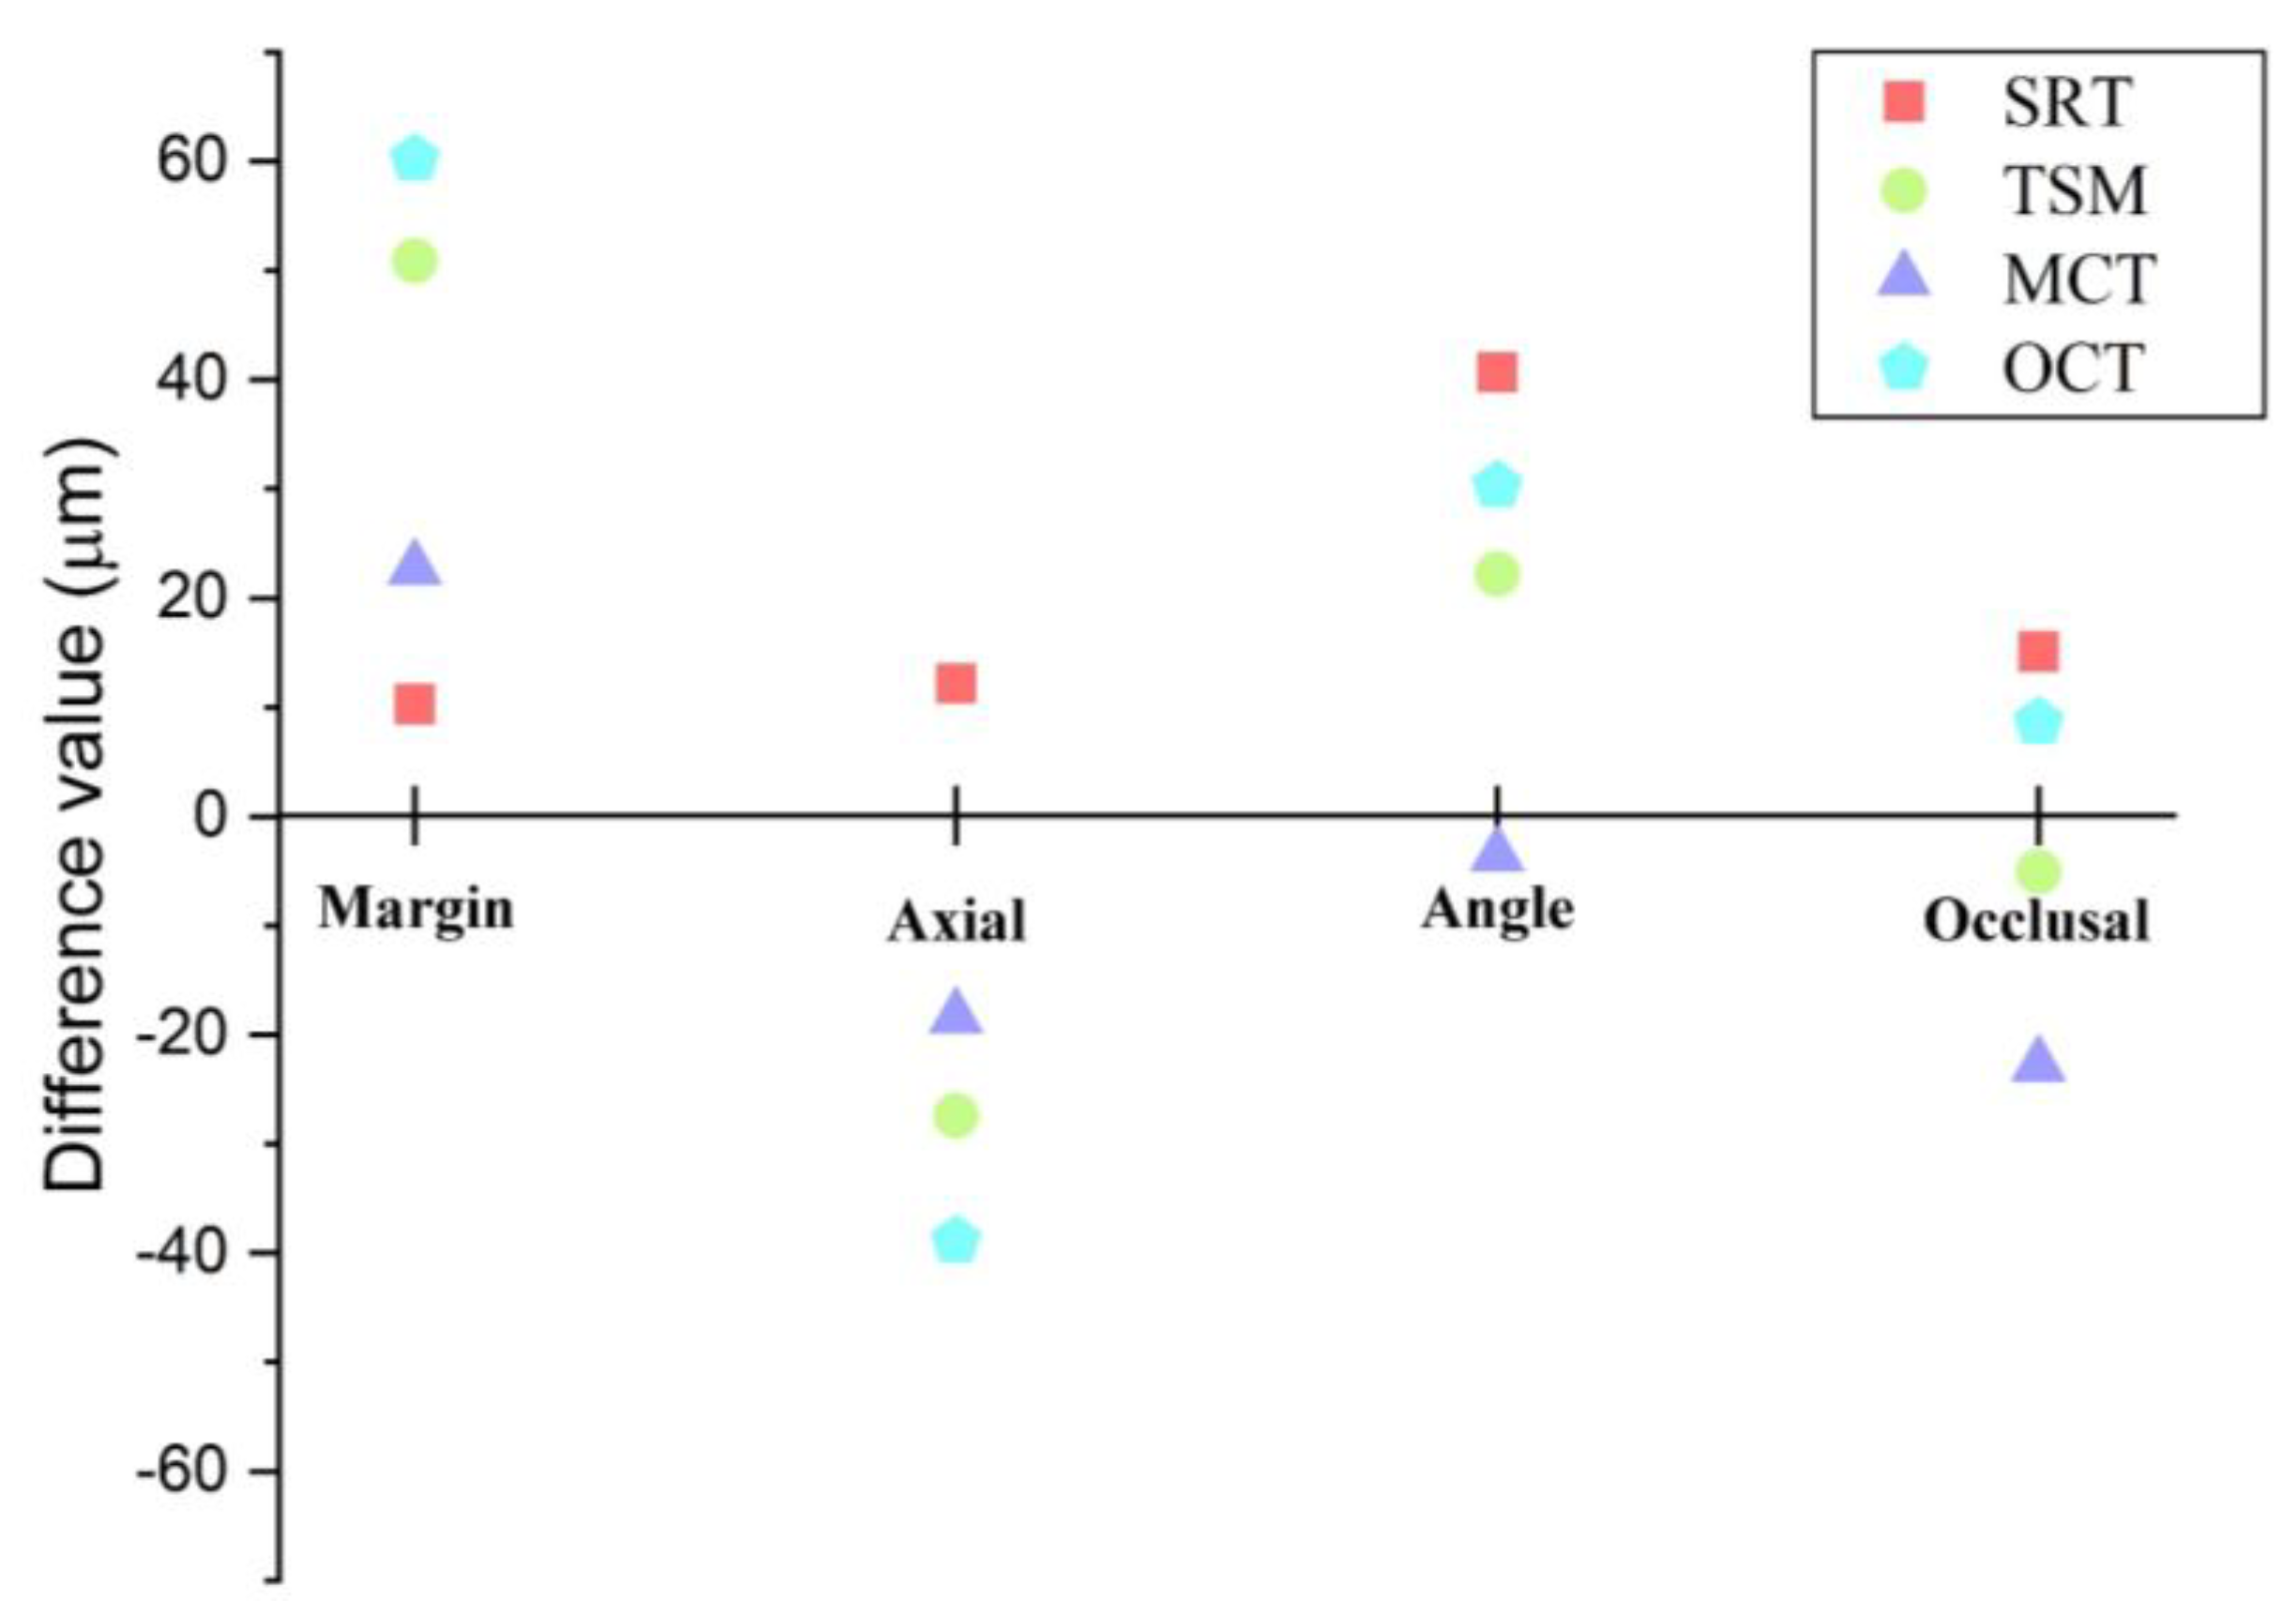

3. Results

| Test method | Margin | Axial | Angle | Occlusal |

|---|---|---|---|---|

| CSM | 23.2 ± 5.3 a | 83.7 ± 19.8 a | 87.9 ± 17.2 a | 125.4 ± 13.7 a |

| SRT | 33.5 ± 12.1 a,b | 95.9 ± 52.9 a,b | 128.6 ± 17.3 b | 140.5 ± 33.3 a |

| TSM | 74.1 ± 26.1 c | 56.3 ± 30.1 c | 110.1 ± 13.9 c | 120.3 ± 20.9 a |

| MCT | 45.9 ± 25.9 b | 65.3 ± 47.7 c,b | 84.3 ± 20.2 a | 102.6 ± 12.8 b |

| OCT | 83.4 ± 22.1 c | 44.8 ± 14.5 c | 118.2 ± 22.2 b,c | 134 ± 18.9 a |